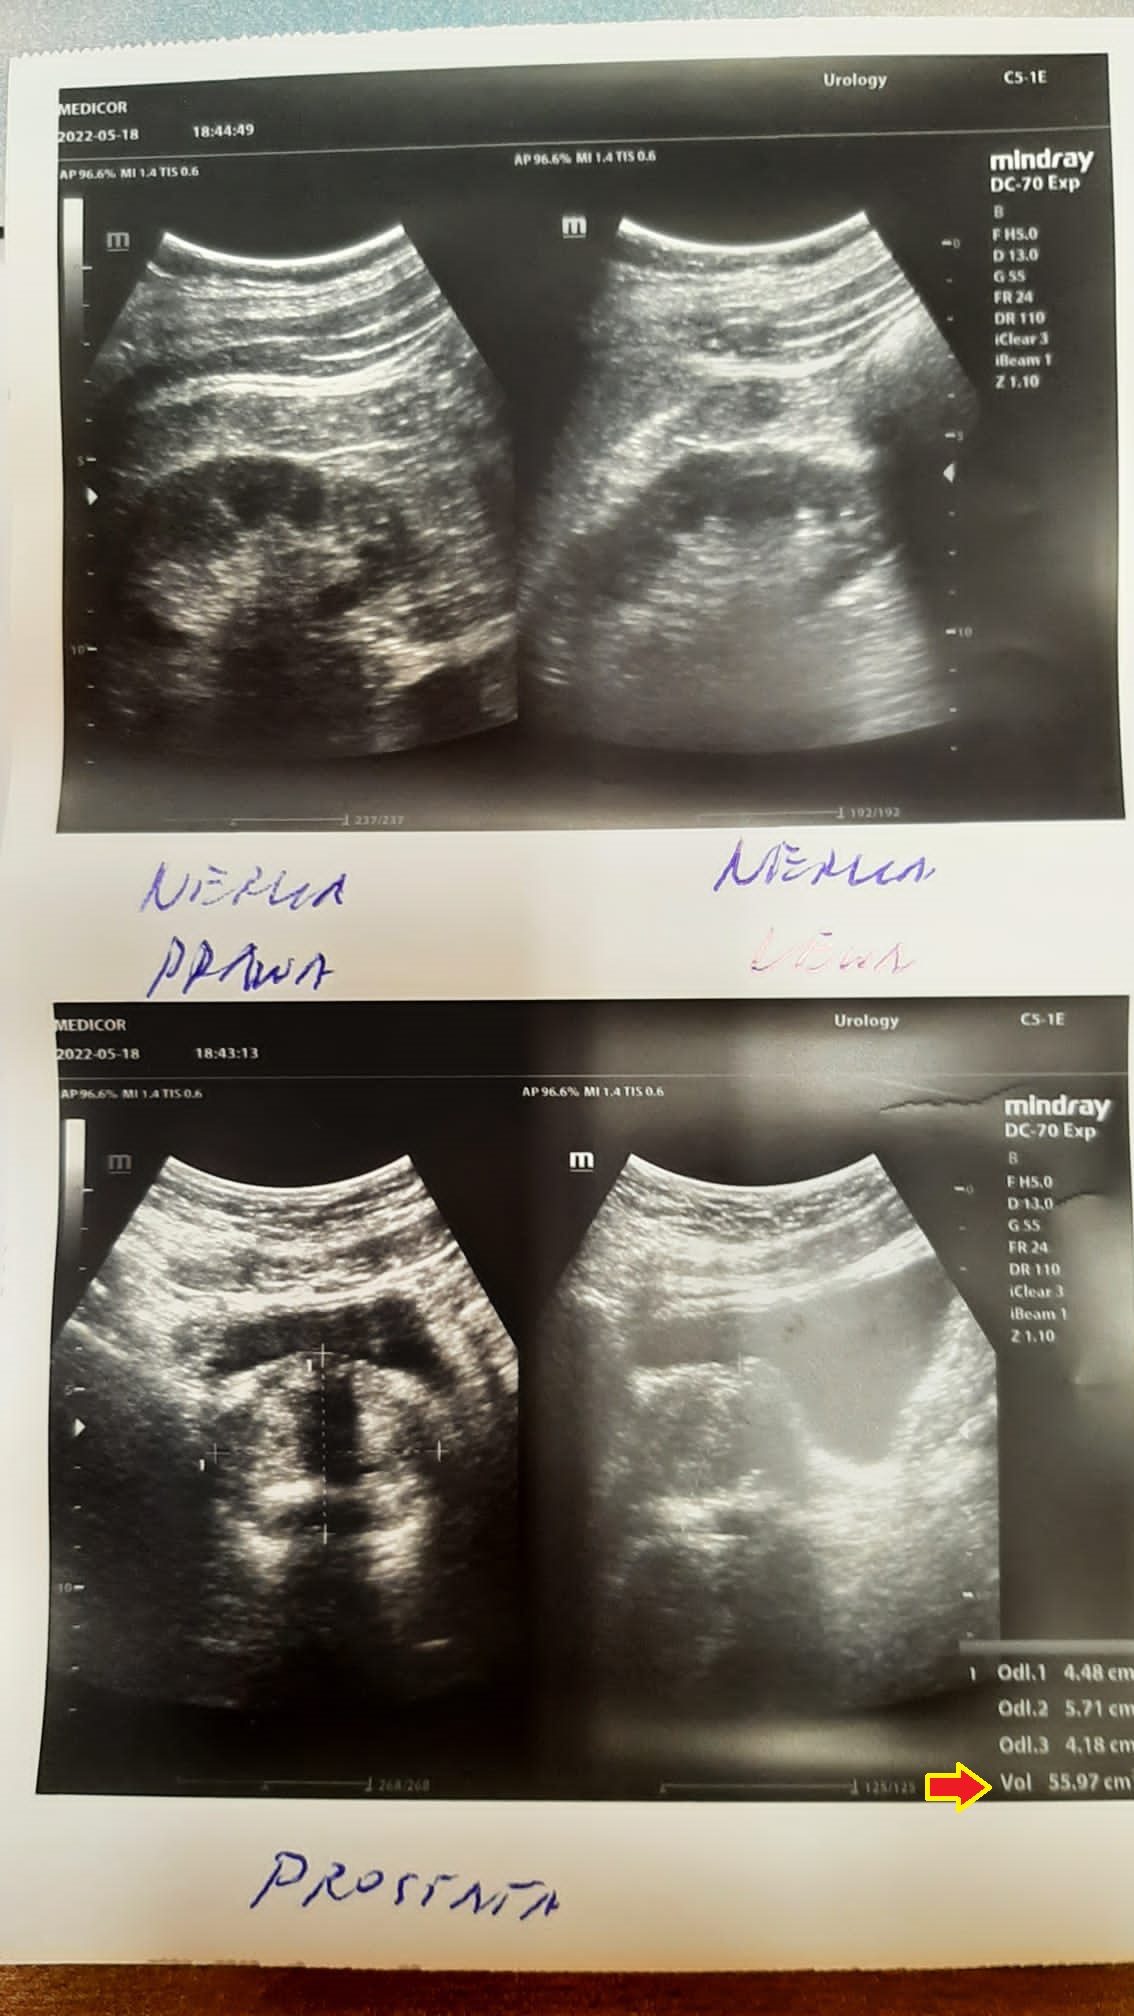

EFEKT PREPARATU NA PRZEROST GRUCZOŁU KROKOWEGO

Mężczyzna lat 50 z przerostem gruczołu krokowego, mimo iż to łagodna hiperplazja, odczuwał ból i dyskomfort przy oddawaniu moczu. Objętość gruczołu krokowego w dniu diagnozy wynosiła 78,21 ml (78,21 cm3). Po nieudanych próbach z finasterydem, podjęto próbę zmniejszenia gruczołu preparatem, jak widać ze zdjęć kontrolnych USG z sukcesem – znaczne zmniejszenie już po 2,5 miesiąca terapii do 55,97 ml (55,97 cm3).